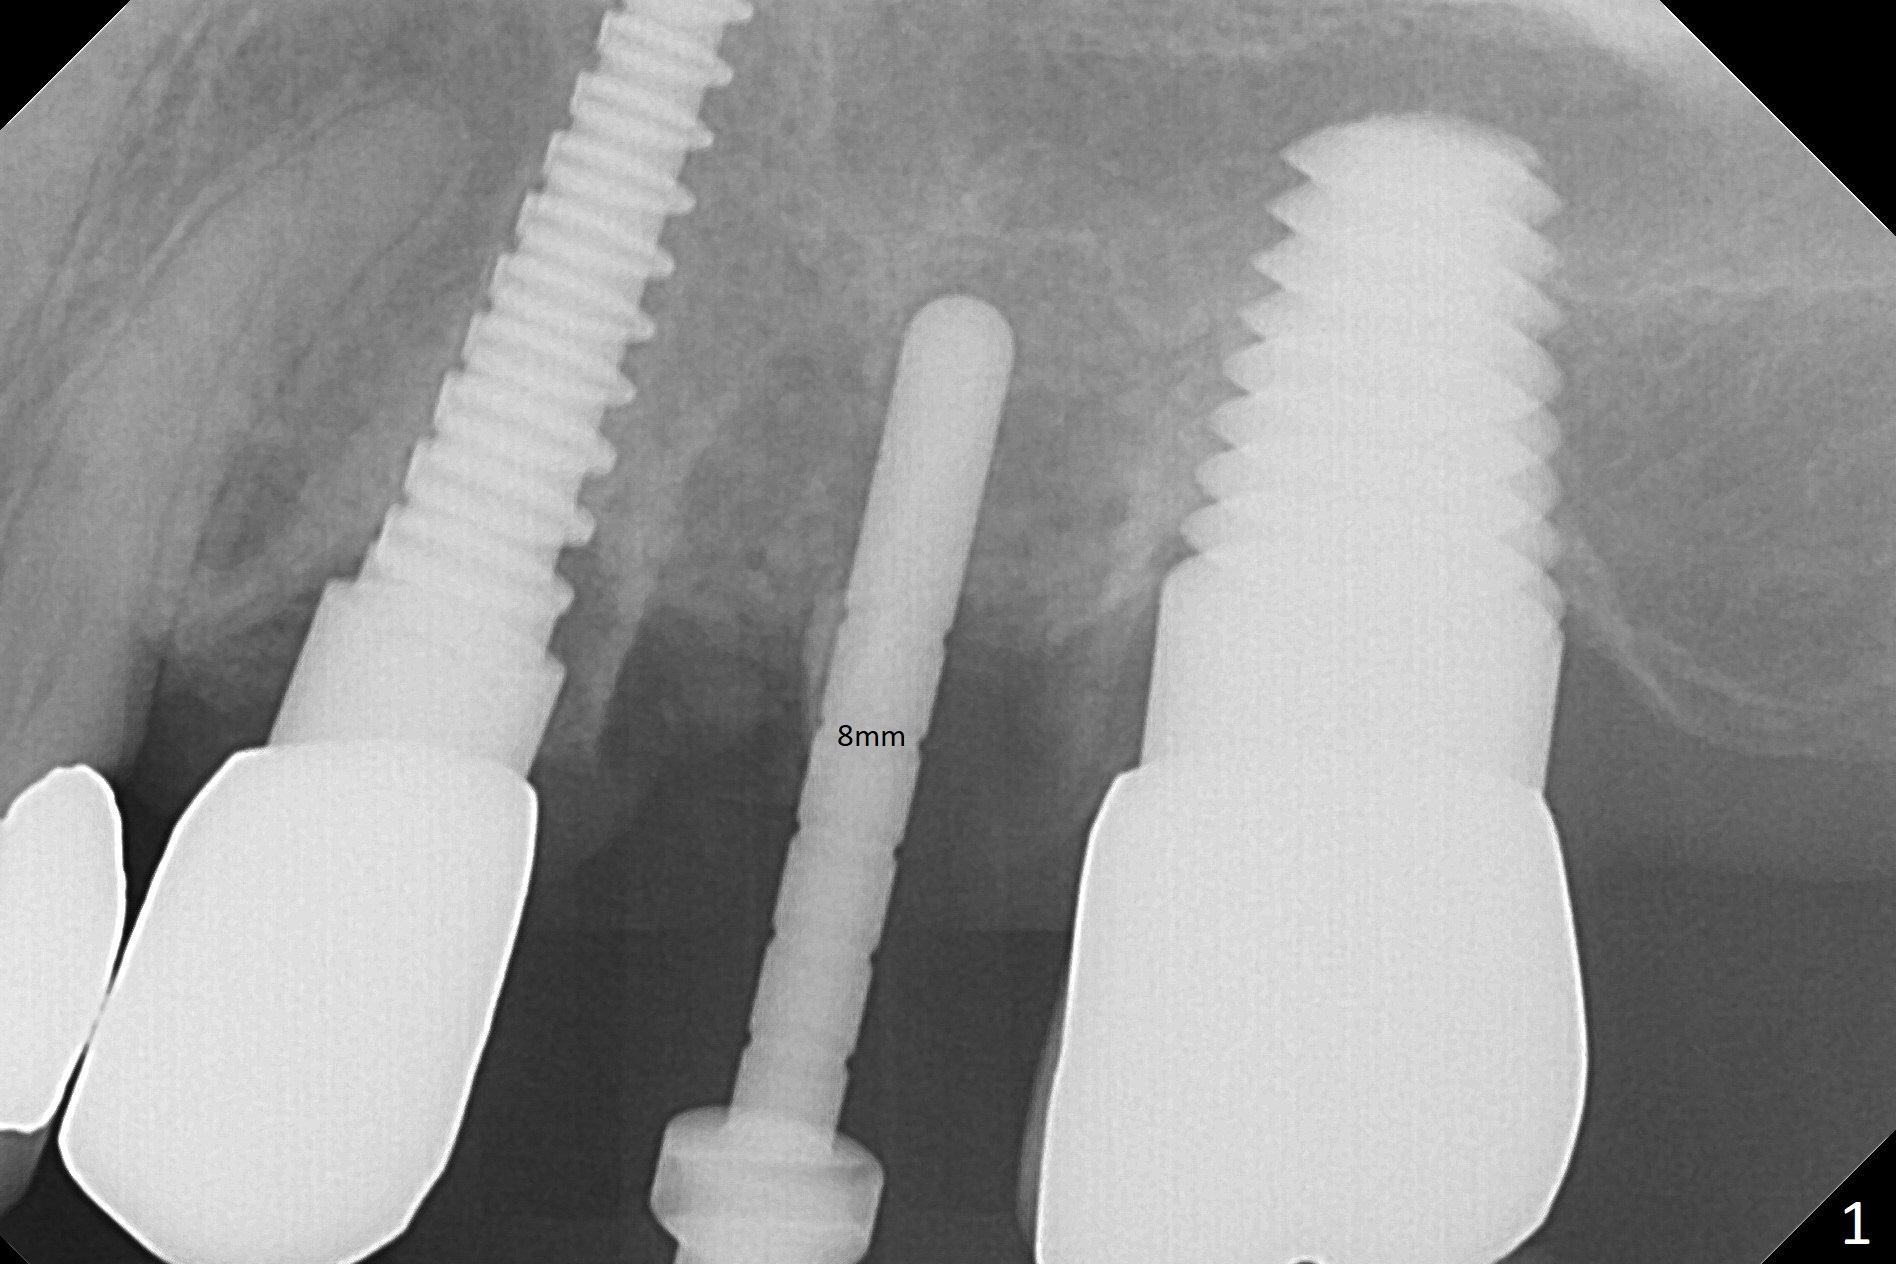

Initial osteotomy in the septum of the tooth #14 is 9 mm, approximately 2 mm from the sinus floor (Fig.1).  Subsequent osteotomy depth is 11 mm, followed by insertion of a 4.5x11 mm dummy implant (Fig.2).  After use of Magic Drill (MD) 4.8 mm for 9 mm, a 5x11 mm IBS implant is placed with sinus lift without additional bone graft (Fig.3 *).  In contrast, autogenous bone (from MD) and Vanilla Graft are meticulously placed in the remaining socket (+) before and after placement of a 6.5x5.7(2) mm abutment.  An immediate provisional is fabricated to close the sockets.  There is buccal tenderness 1-3 months postop.  There is distopalatal implant thread exposure.  A healing abutment (5.5x2 mm) is placed.  CT confirms thin buccal plate (Fig.4,5).  It appears that the implant should have been as palatal as possible.  The tenderness remains for the next 2 weeks.  When the healing abutment is removed, the implant seems to have been placed shallow, ~ 1 mm subgingival (Fig.6).  With local anesthesia, the implant is reversed to clean the coronal threads with Titanium brush and copious irrigation (Fig.7).  The implant is then placed ~4 mm subgingival (Fig.8) and slightly subcrestal (Fig.9,10).  It appears that the postop bone loss (Fig.9 *, as compared Fig.1,2) makes the implant look to be placed too shallow.  When the implant is being placed deeper, the buccal plate feels intact.  The early periimplantitis is apparently due to postop bone loss more than buccal placement, although certain degree of buccal bone resorption must occur.  A 6x4 mm healing abutment is placed.  Left facial swelling develops 2 days post implant elevation (Fig.11,12, as compared to preop (Fig.13)).  The left maxillary sinus cloud (Fig.12) appears to be a false positive finding, since the same feature exists prior to implant elevation (Fig.13).  Both sinuses look clear prior to implant elevation (Fig.14).  Amoxicillin switches to Augmentin and Flagyl, since the patient is reluctant to have the implant removed.  Finally the sinus infection is under control.  The patient feels left facial swelling 9 months postop (5 months post elevation) and reports left nasal discharge ~ 1 month earlier.  There is mild buccal plate tenderness.  The implant seems to be buccally placed (Fig.15,16), although there is no significant change radiographically (Fig.17).  The implant is removed with bone graft (Fig.18 *).  To avoid complication and failure, an immediate implant at the upper 1st molar should be short and placed deep.